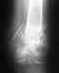

Пациент девушка, 1992 г.р. 11 декабря 2010 года в результате ДТП имеем перелом средней нижней правой третьей большой берцовой кости.

операцию сделали 15 декабря 2010, собрали, поставили пластину. Периодические снимки приложены: 24.12.2010 - сразу после операции 18.06.2011 - промежут. снимок 7.12.2011 - последний снимок. Сейчас диагноз звучит так: Диагноз- сросшийся перелом средней нижней правой третьей большой берцовой кости с наличием пластины Хромота, опираться на ногу невозможно, Ходить запрещают, предлагают ждать еще 2 месяца. Есть мнение, что перелом не сросся(?). Просьба прокомментировать адекватность произведенного вмешательства и перспективы,лечение. Вероятно требуется повторное вмешательство.